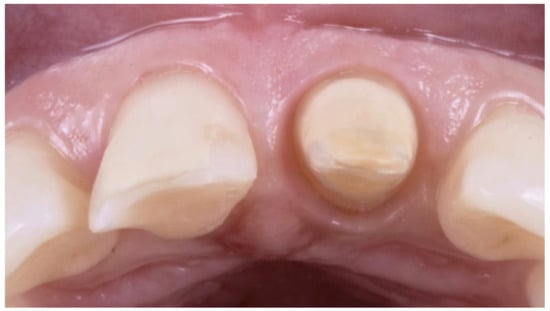

- Primary progressive reduction: This procedure is performed by using the bur with an inclination of 30° so that only the final part of the bur is in contact with the tooth structure. The bur is kept more coronal than the previously measured depth of the gingival sulcus of that site. In this way, the tissue of the root surface and a small component of the internal part of the gingival sulcus is removed. This reduction will result in a small step at the level corresponding to the tip of the bur. At this point, the preparation is “bur-shaped” as with most of the complete crown techniques (Figure 3).

- Secondary progressive reduction: The previously performed reduction of tooth structure and the push of the bur on the gingival margin, together with the unavoidable gingitage, will result in an augmented space between the tooth structures and the gingival margin. This allows the clinician to obtain better vision and access to the deepest parts of the sulcus and, therefore, to see and remove any calculus, steps, grooves, or undercuts from the root surfaces. Using a “toe-heel” technique, the apical part of the root surface is structured, creating the edgeless profile of this preparation. Then, the coronal portion of the abutment is reduced by using a bur with reverse angulation. In this phase, it is also necessary to connect the different reduction planes created during the various stages (Figure 4).